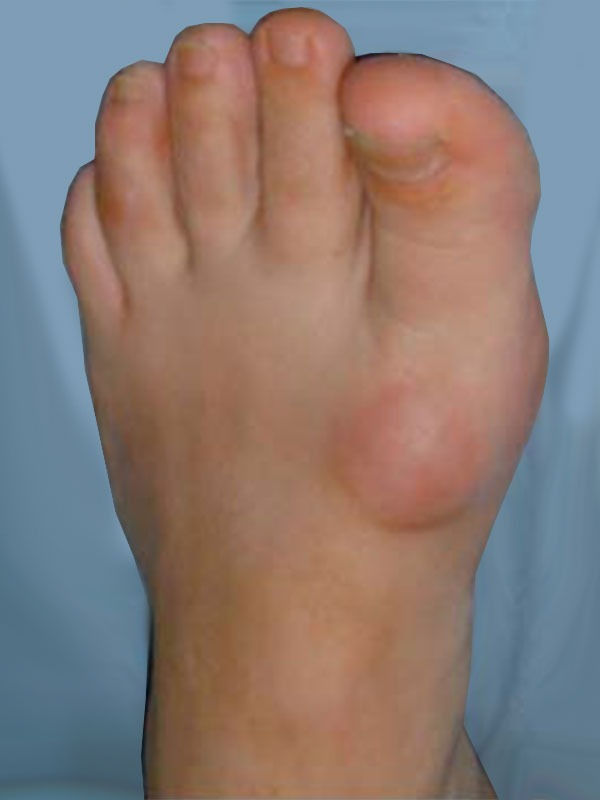

Types Of Big Toe Surgery . The corrective surgery for bunion is known as a metatarsal osteotomy or bunionectomy. The procedure involves an incision in the skin and removal of excess bone with the aid of orthopedic tools that cut away the bone spurs. A first mtp joint fusion is a surgical procedure to treat arthritis of the big toe. Big toe arthritis (also known as hallux rigidus) can cause pain and swelling and lead to difficulty. A keller’s arthroplasty is a surgical procedure to remove bone from the spot where your big toe joint meets the metatarsal bone and replace it with soft tissue. There are four main types of bunion surgery: This procedure is often done. There are multiple techniques, but all involve cutting the bones and repositioning. A cheilectomy is a surgical procedure to remove excess bone from the joint of your big toe, also called the dorsal metatarsal head. Cheilectomy is an operation of the metatarsophalangeal (mtp) joint, where the big toe bends and attaches to the foot. Toe joint replacement is surgery to remove a damaged toe joint and replace it with an artificial (manmade) joint. Your surgeon will make a few small incisions (cuts) in your foot and toe bones.

A keller’s arthroplasty is a surgical procedure to remove bone from the spot where your big toe joint meets the metatarsal bone and replace it with soft tissue. There are four main types of bunion surgery: Big toe arthritis (also known as hallux rigidus) can cause pain and swelling and lead to difficulty. Your surgeon will make a few small incisions (cuts) in your foot and toe bones. A cheilectomy is a surgical procedure to remove excess bone from the joint of your big toe, also called the dorsal metatarsal head. There are multiple techniques, but all involve cutting the bones and repositioning. Toe joint replacement is surgery to remove a damaged toe joint and replace it with an artificial (manmade) joint. Cheilectomy is an operation of the metatarsophalangeal (mtp) joint, where the big toe bends and attaches to the foot. The corrective surgery for bunion is known as a metatarsal osteotomy or bunionectomy. The procedure involves an incision in the skin and removal of excess bone with the aid of orthopedic tools that cut away the bone spurs.